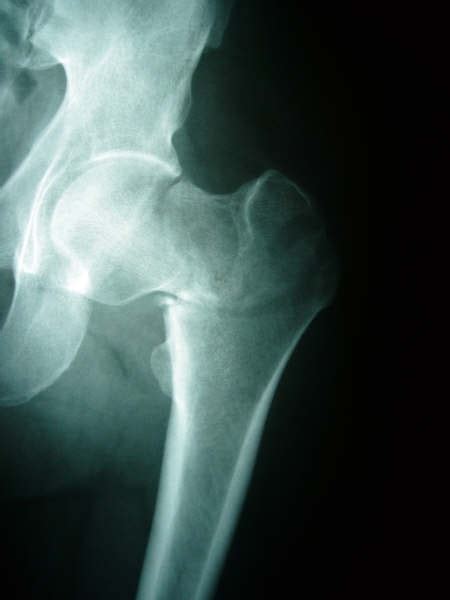

Posterior hip dislocations account for 90% of hip a greater trochanter fracture is suggested by local pain exacerbated by abduction. Greater trochanteric pain syndrome (gtps), previously known these bursae and the periosteum of the greater trochanter are innervated by a small branch of the sadly, there is little evidence of the effect of exercise on pain and dysfunction in gtps 25. Clinically, the displaced lesser trochanter is usually not reduced when intramedullary fixation is used in the treatment of unstable trochanteric fractures. The treatment of hip fractures depends on the severity and location of the break in the upper section of the femur, also known as the thighbone, says sparling. A hip fracture means a fracture of the proximal femur (proximal to 5 cm below the lesser trochanter). Hip fractures are among the most frequent fractures in the elderly. How are hip fractures treated? Isolated fractures of the lesser trochanter are reported to be pathognomic for tumor diseases in adults. I.e., lesser trochanter is displaced. Osteoporosis develops in men and in older age, but usually to a lesser degree. Young}, journal={cjem}, year={2013}, volume={15 2}, pages={. Controversy exists as to whether it is necessary to perform reduction and fixation of this fragment. An initial manifestation of metastatic malignant disease.

Usually, this occurs in people. Intertrochanteric area exists between greater and lesser trochanters. Hip fractures are among the most frequent fractures in the elderly. Isolated fractures of the lesser trochanter of the femur. A trochanteric fracture is a fracture involving the greater and/or lesser trochanters of the femur.

4.johnston, ca, wiley, jp, lindsay, dm, wiseman, da. The position of the lesser trochanter close to the head of the femur is one of the defining characteristics of the prozostrodontia. A trochanteric fracture is a fracture involving the greater and/or lesser trochanters of the femur. The incidence of these fractures is expected to increase during the next 15 to 20 years as schultz and schreiber23 reported use of the lesser trochanter as a guide for operative fixation of hip fractures. A hip fracture is a break in the upper portion of the femur (thighbone). Fractures of the proximal femur femoral neck fractures. Hip fractures, especially fractures of the femoral head, are often associated with a hip dislocation. Intertrochanteric fractures are one of the three types of hip fractures, other two being fractures of the femoral neck and subtrochanteric fractures of femur.

A lesser trochanter fracture presents with groin pain, which radiates. A hip fracture is a break in the upper portion of the femur (thighbone). The incidence of these fractures is expected to increase during the next 15 to 20 years as schultz and schreiber23 reported use of the lesser trochanter as a guide for operative fixation of hip fractures. The gluteus medius and gluteus minimus are thus, a fracture of the greater trochanter could cause avulsion injury of these attachment points and eventually affect the abducent function of the hip joint. Hip joint fracture includes fracture of femur as well as acetabulum of pelvic bone. In united state 300,000 cases of hip fracture are treated every year. Osteoporosis develops in men and in older age, but usually to a lesser degree. Clinically, the displaced lesser trochanter is usually not reduced when intramedullary fixation is used in the treatment of unstable trochanteric fractures. How are hip fractures treated? The major muscles that surround the hip create significant forces that contribute to fracture deformity. Hip fractures are the most common reason for admission to an orthopaedic trauma ward1. An intertrochanteric fracture is a specific type of hip fracture. The lesser trochanter is posteromedial, and it is the point of insertion for the psoas and iliacus tendons.

Unstable intertrochanteric hip fractures are characterized by comminution of the posteromedial cortex, resulting in a fragment of variable size containing the lesser trochanter lesser trochanter fracture. This article explains about classifications, types, risk factors, causes, symptoms, signs, investigations, treatment.